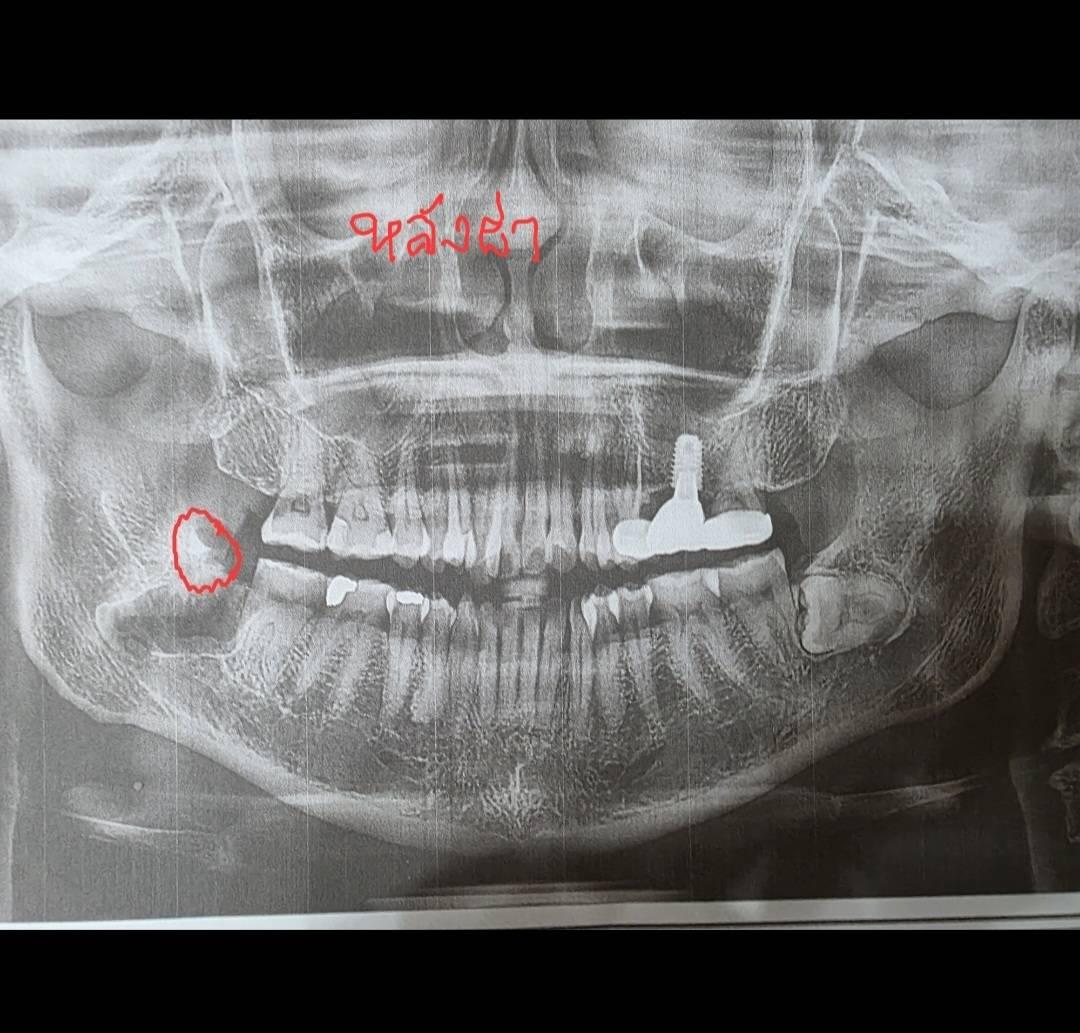

รบกวนผู้รู้ช่วยดูฟิล์มให้ทีค่ะ #ผ่าฟันคุด

อยากทราบว่าหลังผ่าฟันคุดออกข้างนึงแล้ว เศษขาวๆ ที่วงไว้ ใช่เศษฟันแตก (มีการกรอฟันระหว่างผ่าฟันคุดอยู่หลายครั้ง) ที่หลงเหลืออยู่หรือเปล่าคะ